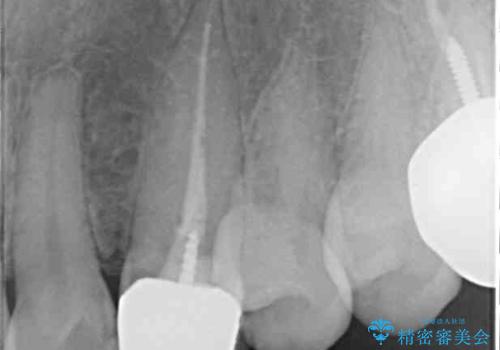

土台の金属を除去してファイバーコアによる土台植立を行い、オールセラミッククラウンにて補綴することとしました。

保険診療では樹脂を用いた素材で製作するため、水分が吸収されやすく、一緒に色素が取り込まれるために変色をしてしまいます。

また、裏打ちに主に銀を用いた金属材料を使用するため、金属自体が黒くなったり、イオンとなり溶け出したりして、歯肉ラインが黒くなってしまうことがあります。